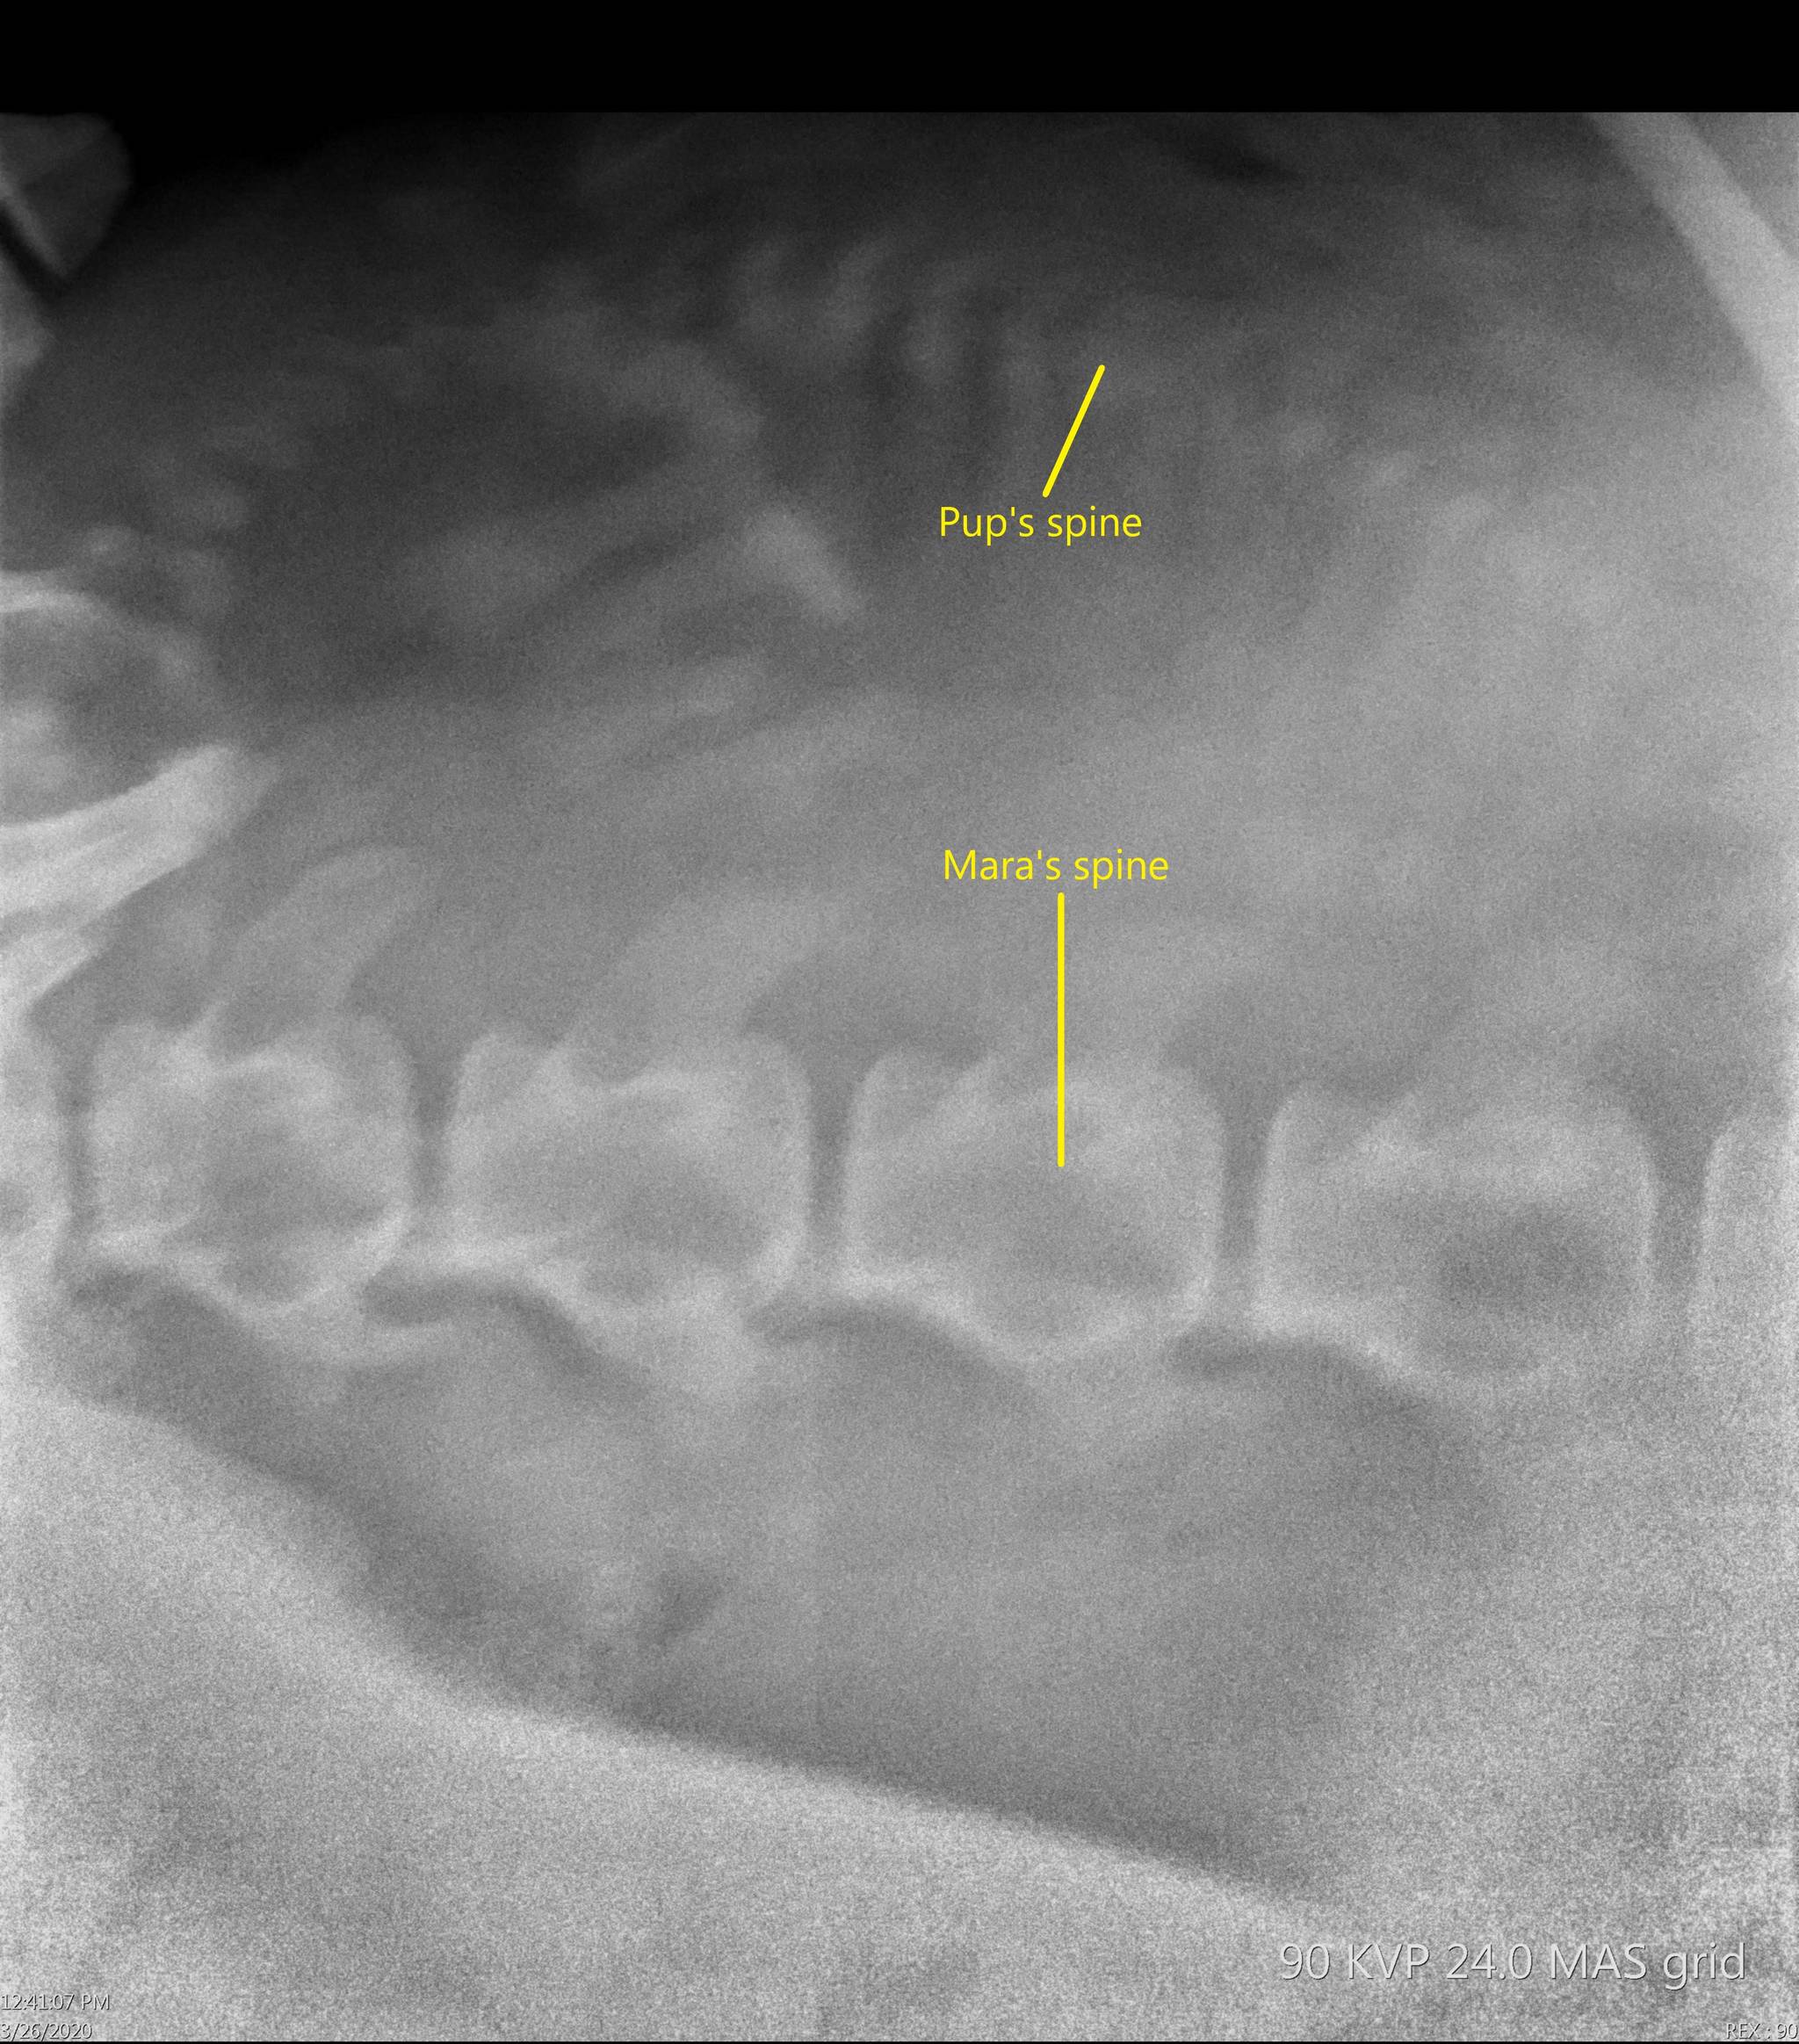

“Estimating a delivery date is imprecise in any species, but in Steller sea lions it is even harder since we have only tracked a few pregnancies,” Dr. Carrie Goertz, director of animal health at the SeaLife Center, said in a Thursday press release. “Nevertheless, I expect Mara to give birth earlier than all of our other births since I was able to detect the developing pup about a month before other cases.”

The study found that animals trained to voluntarily participate in health care had lower cortisol levels than animals that have to be restrained, so mammalogists at the SeaLife Center train Mara and other aquatic mammals to be familiar with medical equipment through frequent ultrasounds and radiographs in order to keep her stress levels low. Hartman said that is also accomplished by gradually introducing the equipment into the animals’ exhibits so that they eventually become desensitized to it.